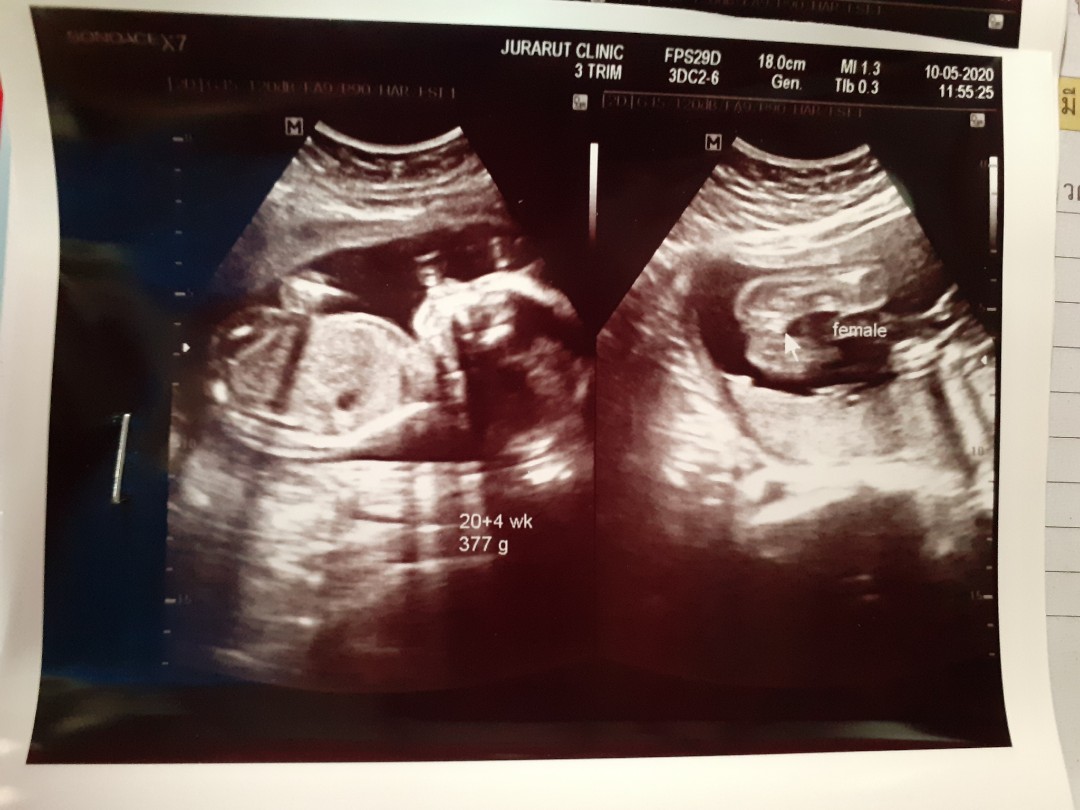

นี่ซาวตอน5เดือนจ้า

บ้านนี้20+1วีคจ้า